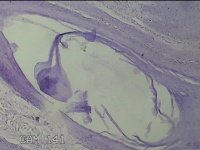

后颈部皮肤结节

性别

男

年龄

45岁

临床诊断

皮肤结节病

一般病史

发现后颈部皮肤结节半年余。

标本名称

大体所见

灰白粉红色组织1.7x0.9x0.3cm一块,表面带梭形皮肤1.7x0.9cm,皮下见结节1.5x1.1cm一个,切开结节呈实性,切面灰白粉红色,质软。